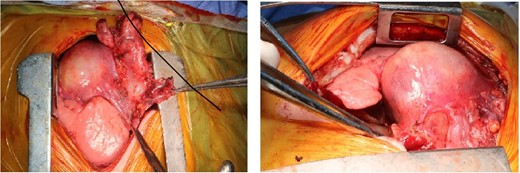

The mass was attached to pericardium, compressing the right atrium and encased the right phrenic nerve (Fig. 3). The mass en-bloc excision and thymectomy revealed multiloculate well-defined cyst measuring 6 cm in maximum dimension. Upon opening the cyst, and the pericardium yellowish sebaceous and cheesy material was found and identified as ruptured mature cystic teratoma with inflammatory reaction. Microscopy showed a ruptured mature cystic teratoma with inflammatory reaction (showing an unremarkable squamous, respiratory and gastric types epithelium, mature adipose tissue, smooth muscle tissue, and skin adnexa), with an unremarkable thymic tissue and no immature elements or malignancy.